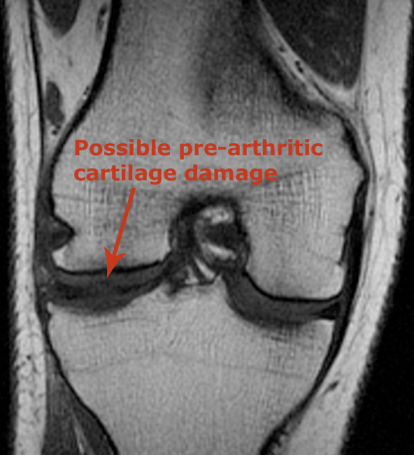

This image is from the front of the knee. That little tiny black spot amid the charcoal-colored stuff could be an indication of damaged cartilage, but the Dr. won’t know until he can go in and take a look.